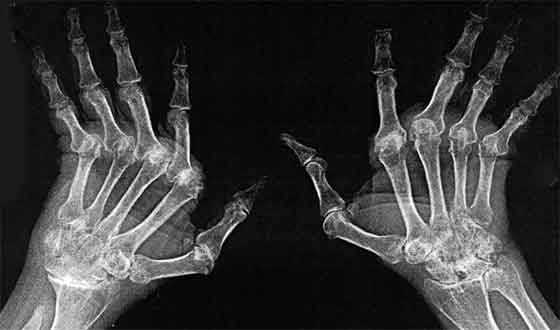

Рентген